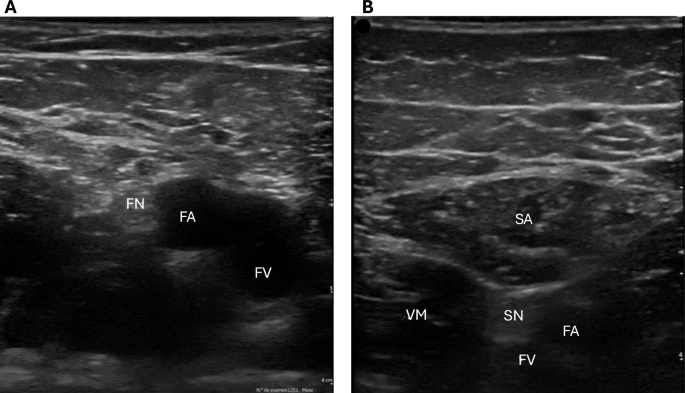

For the localization of the FN, the ultrasound probe was initially placed over the Scarpa’s triangle, using the femoral artery pulse as a primary anatomical landmark. Medial to the artery, the femoral vein was identified. A transverse (short-axis) scan of the nerve was performed to assess the CSA, using the ultrasound device’s tracing tool to outline the inner boundary of the hyperechoic nerve edge. As shown in Fig. 1A, the FN was clearly identifiable alongside the femoral artery and vein. Perpendicular measurements were used to assess the subcutaneous tissue thickness and the distance from the skin to the FN (in centimeters), ensuring accurate localization and evaluation. Nerve depth was defined as the perpendicular distance from the skin surface to the superior (superficial) border of the nerve.

(A) Femoral nerve alongside the femoral vessels. FN: femoral nerve. FA: femoral artery. FV: femoral vein. (B) Saphenous nerve adjacent to the sartorius muscle. SA: sartorius. VM: vastus medialis. SN: saphenous nerve. FA: femoral artery. FV: femoral vein.

For the localization of the SN, the ultrasound probe was positioned transversely on the medial aspect of the mid-thigh, using the course of the saphenous vein as an anatomical reference. The SN was identified within the path of the sartorius muscle. A transverse (short-axis) scan was performed to assess the CSA. As illustrated in Fig. 1B, the ultrasound image clearly reveals the SN near the saphenous vein and surrounding muscular structures. Additionally, calipers were used to measure the subcutaneous tissue thickness and the shortest distance (in centimeters) between the SN and the skin surface.